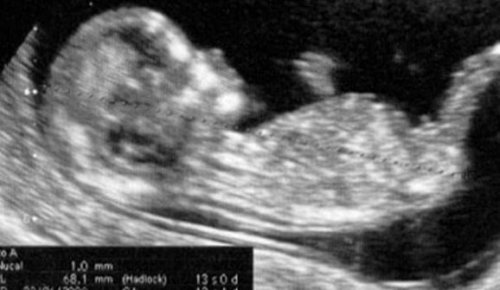

Die Vorsorgeuntersuchung, die normalerweise am Ende des ersten Trimesters gemacht wird, kann auch in der 13. Schwangerschaftswoche noch durchgeführt werden.

Sie ist die letzte Untersuchung einer Reihe von Untersuchungen, die zum ersten Trimester einer Schwangerschaft dazu gehören.

Die Untersuchungen für das erste Trimester sind mit dieser Untersuchung also endlich abgeschlossen.

Ab nun gibt es nur noch wenige Vorsorgeuntersuchungen – zumindest fürs erste.

Bei den monatlichen Vorsorgeuntersuchungen wird die Entwicklung des Kindes kontrolliert und es wird der gesundheitliche Zustand der Mutter überprüft.